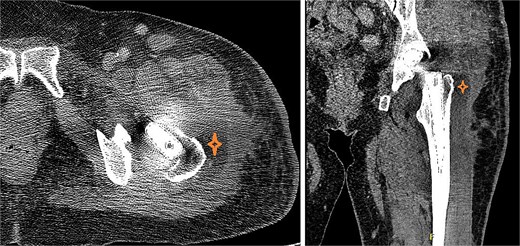

At the 2 weeks post-op visit for suture removal, she reported fever reaching 38.5°C for a few days with slight wound erythema. Blood tests showed WBC count 10 900 (83% neutrophils), ESR >120, CRP 310, Procalcitonin 1.24. Computed tomography (CT) scan of the hip with contrast (Fig. 3) showed deep fluid collection containing gas pockets abutting the left proximal femur, extending from subcutaneous tissue to gluteus medius and iliopsoas muscles, measuring 7.2 × 6.6 × 14 cm.

CT of the hip with contrast showed peripherally enhancing deep fluid collection (marked with star) containing gas pockets abutting the left proximal femur extending to the subcutaneous tissue and the gluteus medius muscles and measuring 7.2 × 6.6 × 14 cm with overlying skin thickening and fat stranding.